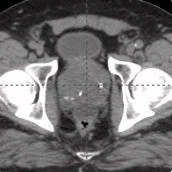

20 cc prostate post-CT showing BioProtect Balloon Spacer, prostate, and rectum.

Post-CT

Image courtesy of Dr. Stan Golin, Radiation Oncologist.